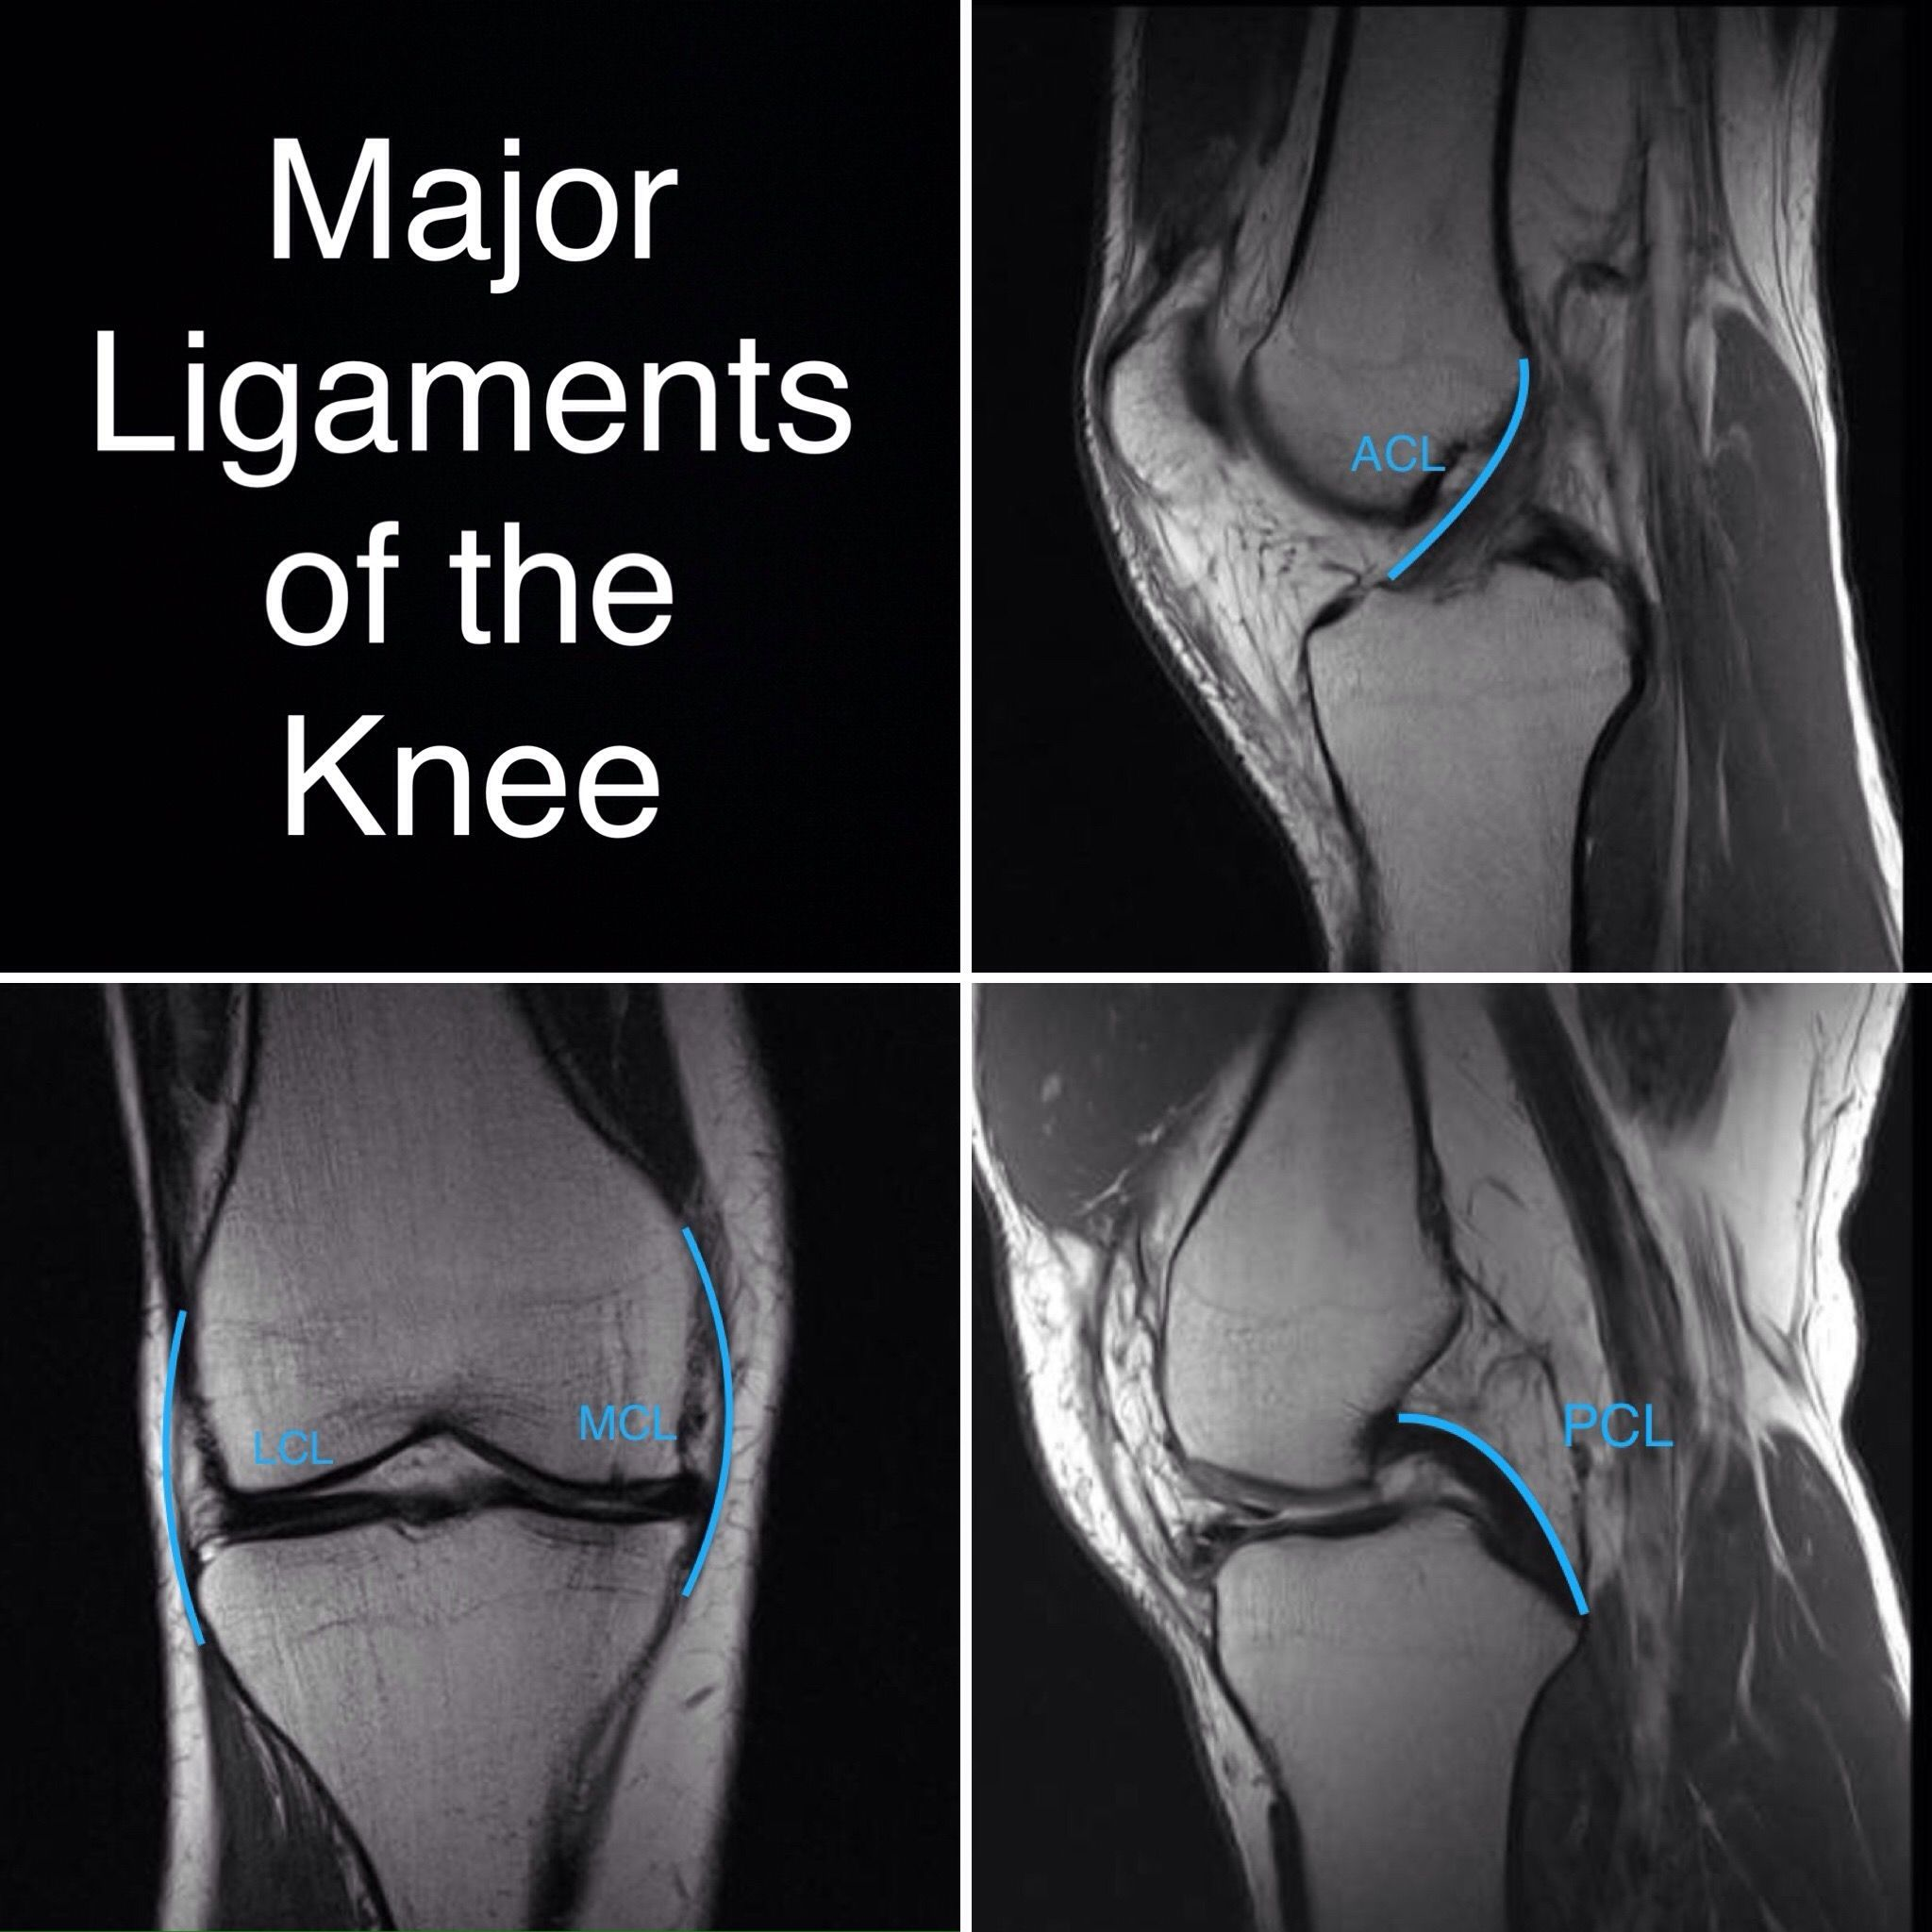

72 一位 22 歲男性病人主訴運動後右膝關節疼痛。圖為本次就診之右膝關節 X 光攝影及磁振造影。最可 能的診斷為何?

(A) Avulsion of medial collateral ligament

(B) Avulsion of lateral collateral ligament

(C) Avulsion of anterior cruciate ligament

(D) Avulsion of posterior cruciate ligament